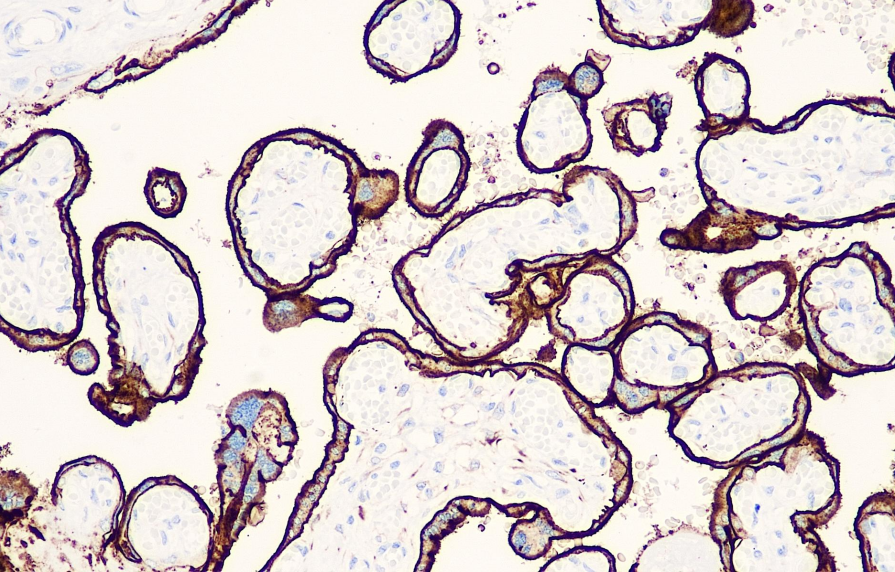

Positive control: Placenta

PLAP is present in normal placenta and is also expressed in ovarian germ cell tumors, testicular tumors, and extragonadal germ cell tumors, including seminoma, gonadoblastoma, yolk sac tumor, and choriocarcinoma. However, PLAP is not expressed in spermatogenic seminoma and immature teratoma. This antibody is primarily used in the study of testicular germ cell tumors and ovarian dysgerminoma.

PLAP antibody reagents can specifically bind to PLAP molecular antigens. Immunohistochemistry kits containing PLAP antibody reagents are suitable for the precise diagnosis of testicular germ cell tumors and ovarian dysgerminomas.